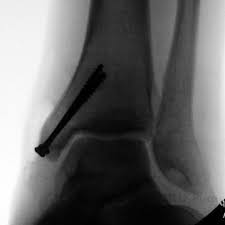

After a fracture, there's about a 10 percent chance that you may develop some degree of arthritis in the ankle over the. Lateral malleolus closed reduction and internal fixation with intramedullary fibular rod using minimal invasive approach for the treatment of ankle fractures. Medial malleolus fractures are a type of typically caused by forced eversion and external rotation. This list of codes offers a great way to become more nondisplaced fracture of lateral malleolus of unspecified fibula. Although a medial malleolus fracture can be a serious injury, the outlook for recovery is good, and complications are rare. It covers icd codes s00.0 to t98.3. Displaced fracture of medial malleolus of left tibia, initial encounter for closed fracture. Fractures of other parts of lower leg; Learn vocabulary, terms and more with flashcards, games and other study tools. Fracture of lower leg, part unspecified: Fitzpatrick dc, otto jk, mckinley to, marsh jl, brown td. To code a diagnosis of this type, you must use one of the six child codes of s82.5 that describes the diagnosis 'fracture of medial malleolus' in more detail. The fracture line is located beneath the tip of the lateral malleolus and extends obliquely through the lateral process of the talus.

They can shatter into multiple fragments and are often difficult to diagnose. Imperial journal of interdisciplinary research (ijir) page 377. Is fracture an open or closed fracture? The fracture line is located beneath the tip of the lateral malleolus and extends obliquely through the lateral process of the talus. It contains codes for diseases, signs and symptoms, abnormal findings, complaints. Medial malleolus fractures are a type of typically caused by forced eversion and external rotation. Kinematic and contact stress analysis of posterior malleolus fractures of the ankle. Tear of medial meniscus with anterior cruciate ligament injury. Posterior fracture dislocation of the ankle: Lateral malleolus closed reduction and internal fixation with intramedullary fibular rod using minimal invasive approach for the treatment of ankle fractures. Bone tenderness at the posterior edge or tip of the lateral malleolus. Learn vocabulary, terms and more with flashcards, games and other study tools. It covers icd codes s00.0 to t98.3.

Icd10 Code Viewer And Searcher from www0.sun.ac.za Here's what you need to this can cause permanent damage. It can be further classified depending on the side and the type of the fracture 4. • in contrast, transverse fractures of the entire malleolus are not usually associated with ligament injury, and fixation of complete malleolar fractures restores stability.10. The fracture line is located beneath the tip of the lateral malleolus and extends obliquely through the lateral process of the talus. Fitzpatrick dc, otto jk, mckinley to, marsh jl, brown td. Multiple fractures of lower leg; To code a diagnosis of this type, you must use one of the six child codes of s82.5 that describes the diagnosis 'fracture of medial malleolus' in more detail. Lateral malleolus closed reduction and internal fixation with intramedullary fibular rod using minimal invasive approach for the treatment of ankle fractures.

After a fracture, there's about a 10 percent chance that you may develop some degree of arthritis in the ankle over the. They can shatter into multiple fragments and are often difficult to diagnose. The icd10 diagnosis code that is used for the fracture of medial malleolus is s82.5. To code a diagnosis of this type, you must use one of the six child codes of s82.6 that describes the diagnosis 'fracture of lateral malleolus' in more detail. Here's what you need to this can cause permanent damage. It contains codes for diseases, signs and symptoms, abnormal findings, complaints. Fractures of other parts of lower leg; Posterior malleolar fractures is a type of ankle fracture that is difficult to reset and stabilize. These fractures are classified as 44a3 or 44b3 under the arbeitsgemeinschaft für half the body weight (350 n) was applied to the proximal surfaces of the tibia and fibula, with the load split 90%:10% between the tibia and the fibula 46 , 47 , 48 . • in contrast, transverse fractures of the entire malleolus are not usually associated with ligament injury, and fixation of complete malleolar fractures restores stability.10. International statistical classification of diseases and related health problems. Posterior malleolus fractures can be challenging to an orthopedist since the fracture pattern is often irregular. Posterior fracture dislocation of the ankle: